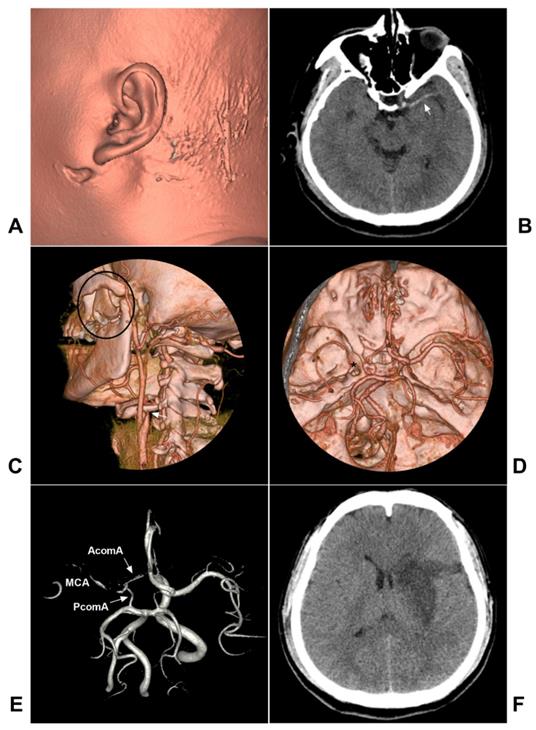

Covered stent deployment

By setting up a direct physical barrier, the covered stent allows the immediate closure of the leakage while maintaining the patency of the parent artery; for extracranial ICA pseudoaneurysm, the covered stent graft has appeal [43, 67, 77]. In Wang et al. (2020), 5 patients with traumatic carotid pseudoaneurysms underwent covered stenting, and complete exclusion of the pseudoaneurysm and patency of the parent artery were maintained during follow-up [78].

During covered stent deployment, to ensure good adherence and avoid endoleak, the stent diameter is selected mainly according to the larger diameter of the proximal and distal ICA, and the length of the stent must be long enough [42, 79]. A typical case is shown in Figure 4.

Figure 4

Covered stent deployment for the traumatic extracranial ICA pseudoaneurysm. A-B: CTA (A) and DSA (B) showed a pseudoaneurysm in the high segment extracranial CIA (arrow in B). C: A covered stent (MicroPort Medical Co., Shanghai, China) crossed the pseudoaneurysm (arrows show the distal and proximal markers). D: After covered stent deployment, endoleak was observable (arrow). E: After the balloon dilation was repeated, the endoleak disappeared. F: X-ray showing the covered stent (white frame). Abbreviations: CTA: CT angiography; DSA: digital subtraction angiography; ICA: internal carotid artery